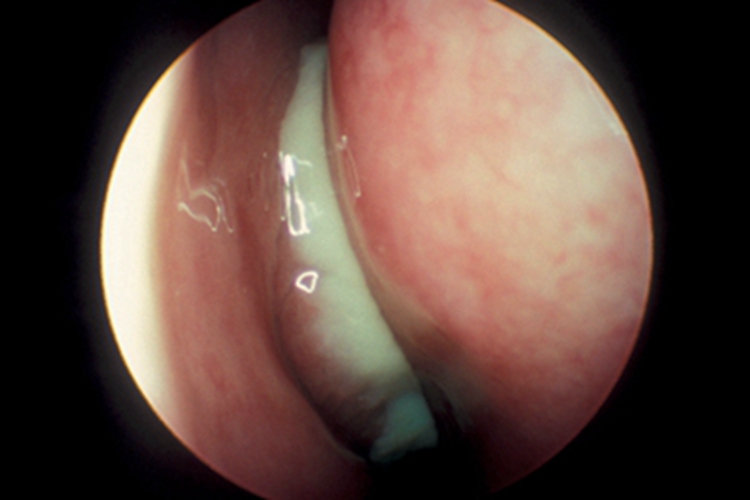

慢性化脓性鼻窦炎可见患者鼻腔黏膜水肿,随病程发展产生息肉样变,形成鼻息肉,可见质地较黏稠的脓性分泌物流出,伴随腐臭气味,干燥后结痂,伴鼻塞、头痛、精神不振等症状。

经规范药物治疗无效、具有明显解剖学异常或发生颅内、眶内并发症的患者可考虑鼻内镜手术治疗。